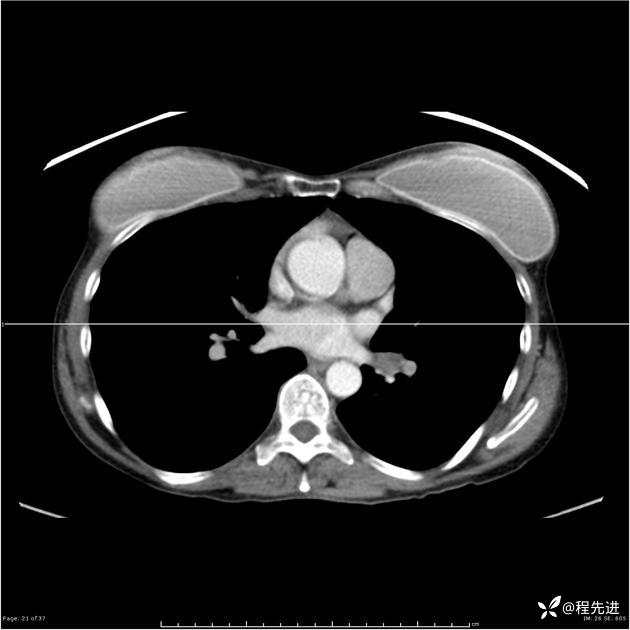

病例女,53岁,气管、左主支气管、下叶支气管内结节,乳头状瘤?期待你的精彩解读

女,53岁

乳头状瘤?